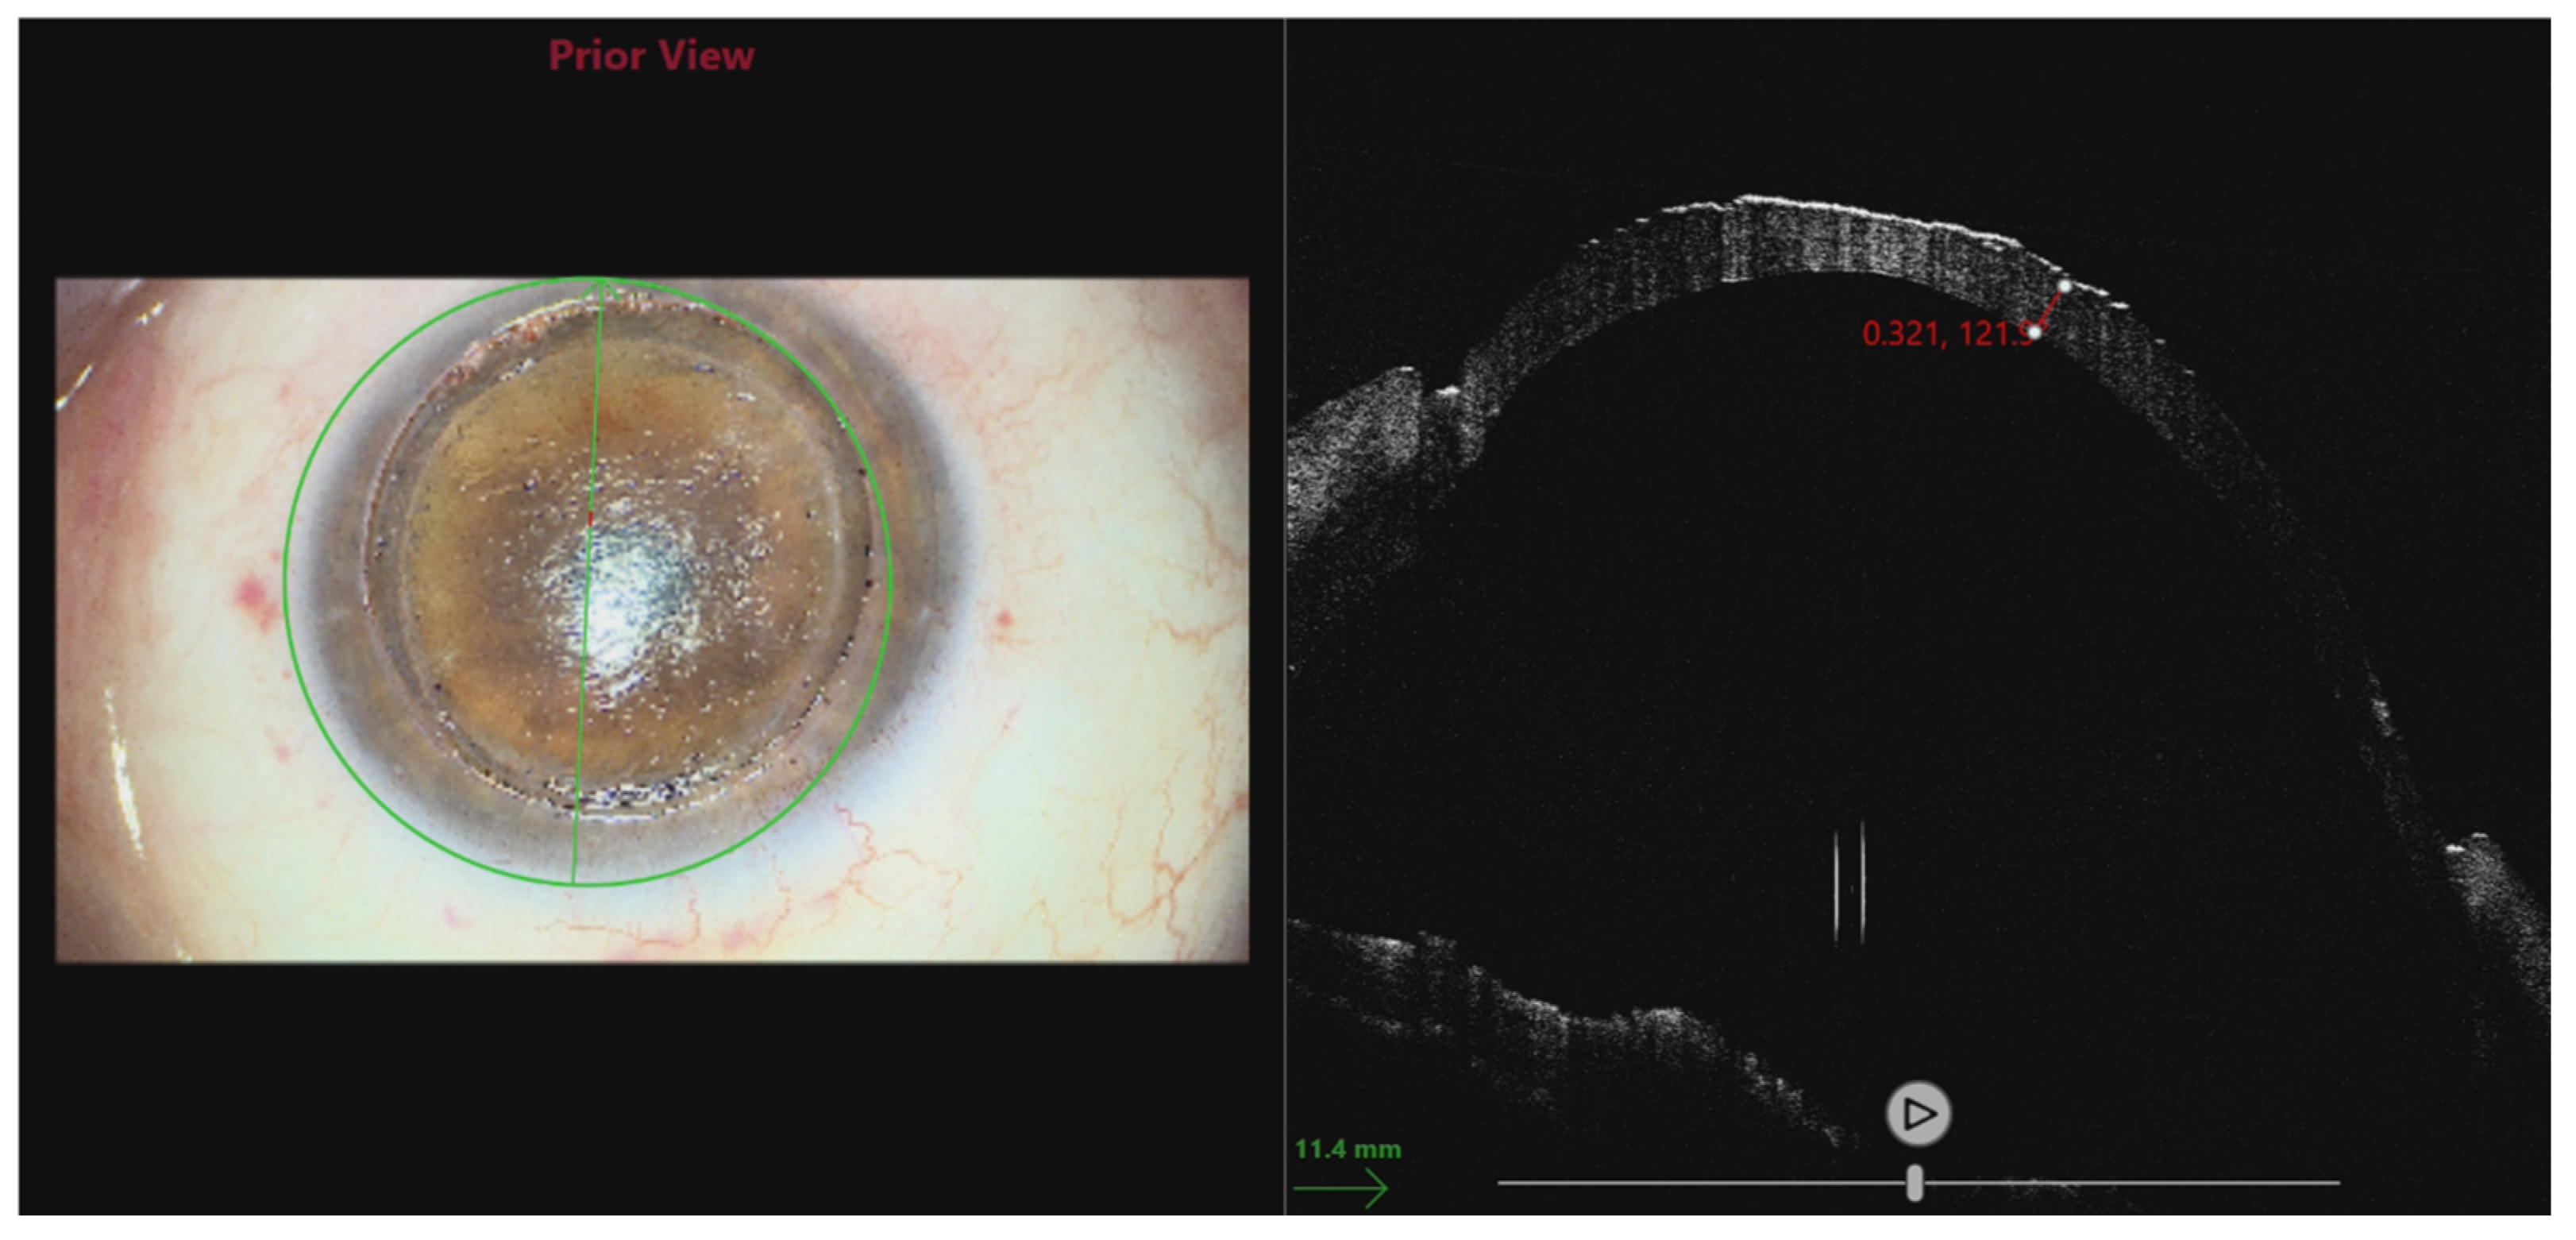

3.5. Use of Intraoperative OCT